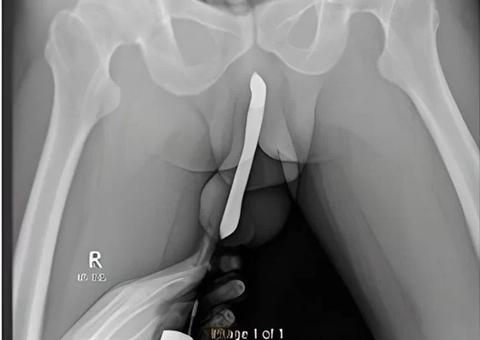

Uma ressonância magnética revelou que o bebê sofre da condição "medula ancorada", que ocorre quando a medula espinhal fica presa em partes do canal vertebral, podendo levar a "estiramentos" na base da coluna.